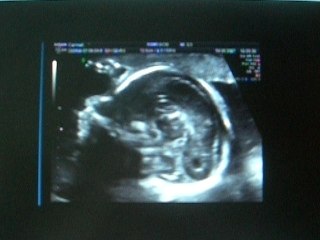

échographie du 6ème mois (3)

Uploaded: 2007-07-19